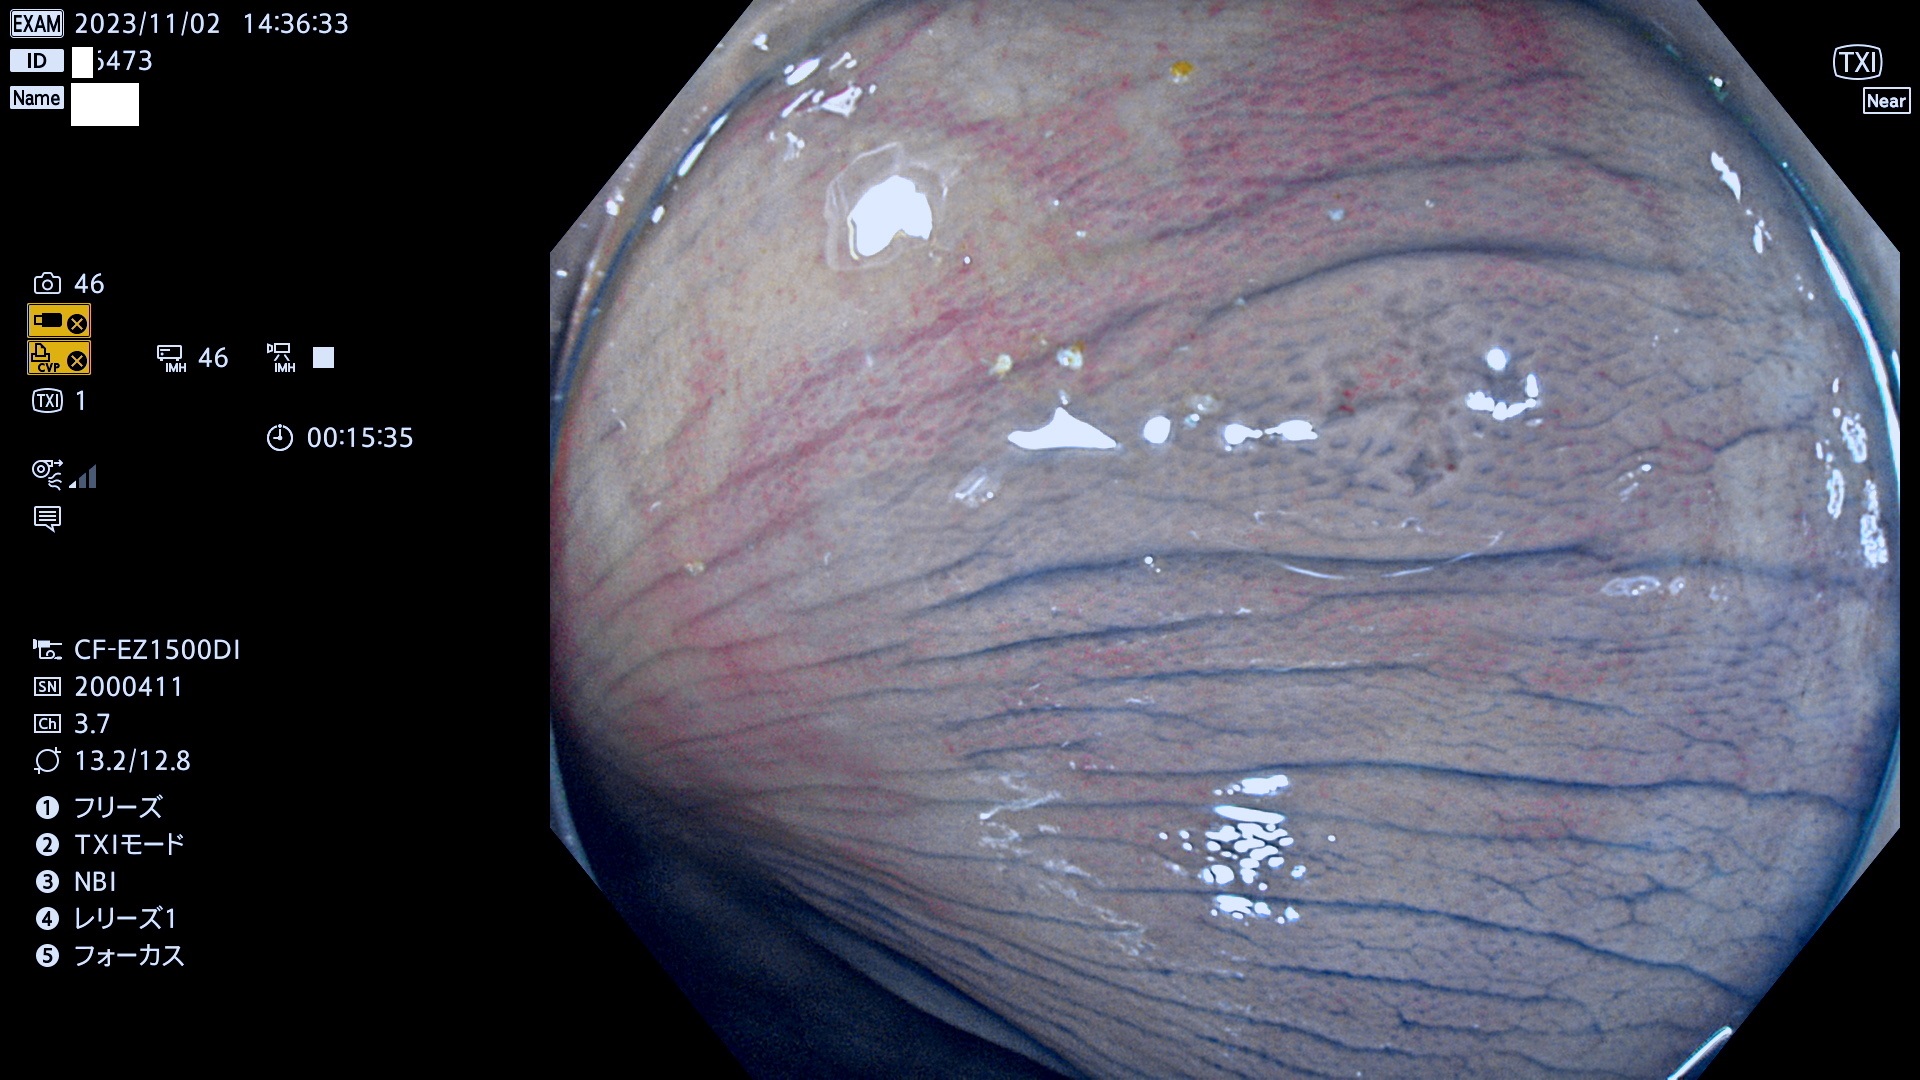

表面型腺腫(Flat Adenoma)の中で、完全に平坦な物をUb、陥凹している物をUcと呼びます。平坦隆起型(Ua)よりも、発見が難しく危険な病変です。このタイプは「内視鏡後・大腸癌の重要犯人」であり、この発見率は「腺腫発見率」よりも、重要な意味があります。

毎週の検査(木・金・土・日)に発見されたUb、Uc型・腺腫を、その週の日曜の夜にUPし1週間、提示します。

抽出の対象期間 2023年11月2日(木)〜11月6(月)の5日間(60件の検査)11件